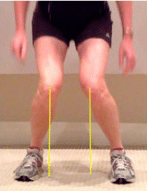

Hip strengthening is also a very important component in resolving ITBS. People with ITBS are found to have hip musculature weakness that causes your knee to cave in into valgus (see picture below). This position predisposes you to injury and it also puts tension on that IT band. For strengthening exercises, check out our videos for lower extremity strengthening and pay attention to exercises like side steps, side-lying hip abduction, clamshells, and stepdowns.